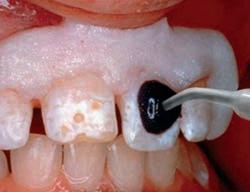

Sable Seek caries indicator contains FD&C dyes, and Seek caries indicator contains D&C dyes in a glycol base. Both are used to stain carious and demineralized dentin.

Seek and Sable Seek caries indicators stain carious and demineralized dentin and can be very useful for difficult-to-see areas, for example; undercuts of preparations, dark dentin, areas along the DE junction, etc. Green Sable Seek caries indicator helps visualization of decay in deep caries cases to help avoid pulp exposures.

PROCEDURE

dentin) with slow-speed round bur or excavator. To control overexcavating near the pulp, remove final portion of caries with hand excavator.